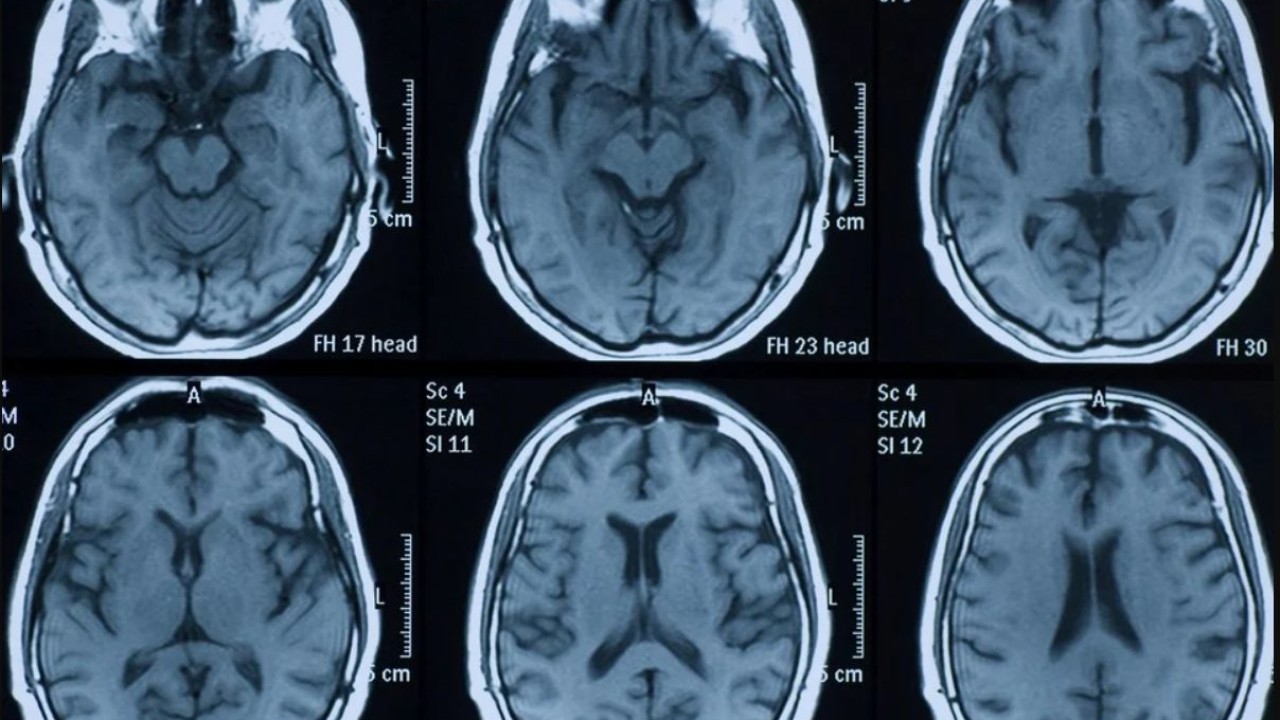

Teknolojinin sürekli gelişmesi ile herhangi bir cerrahi müdahale olmaksızın beyin ile ilgili veriler elde edilebiliyor. Hemen hemen herkes tarafından duyulan

MR (manyetik rezonans görüntüleme), insan beyninde hiç kullanılmayan alan olmadığını rahatlıkla gösterebilir. Başka bir tıbbi veriye göre, beynin %10'unu kullanıyor olsaydık, bitkisel hayatta olacağımızı söylüyor.Başka bir basit denklem aslında bu söylentinin ne kadar saçma olduğunu gösteriyor. Hepimizin bildiği gibi, insan vücudu tarafından üretilen enerjinin yaklaşık %20'si beyni eğitmek için kullanılır. Sadece %10 aktif olan organlar için bu enerji harcaması çok yüksektir. İşte bu yüzden beynimizin %10'unu kullandığımız fikrine artık basitçe efsane deniyor. Dolayısıyla insan beyninin %100 kullanıldığı gerçeği artık ispatlandı.